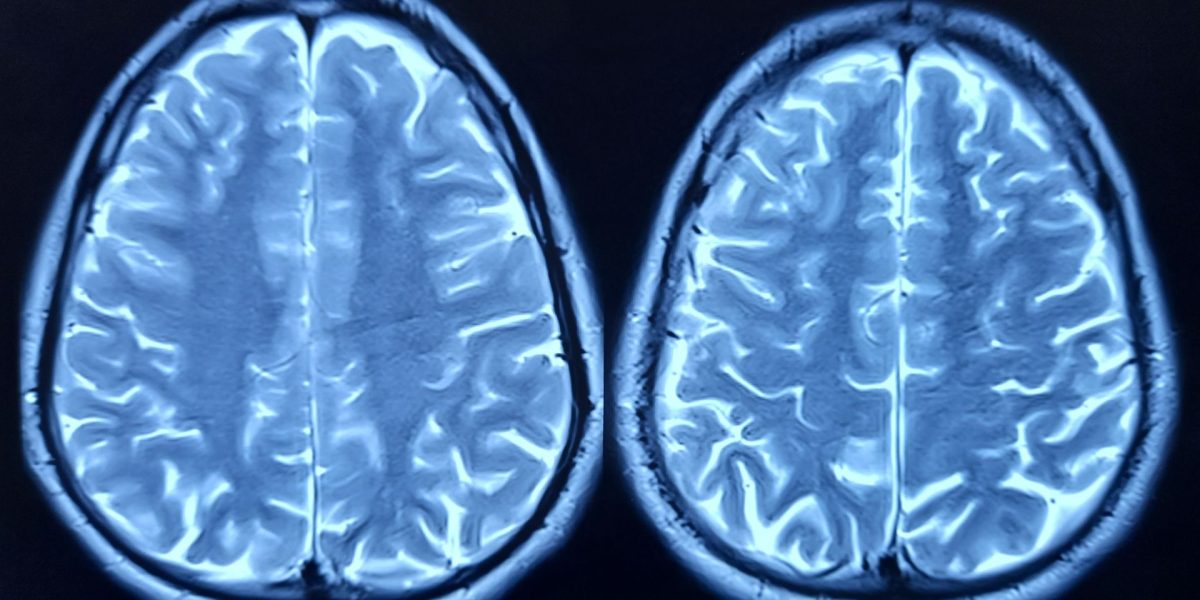

O proteină-cheie ar putea fi responsabilă pentru îmbătrânirea creierului, arată un studiu recent pe șoareci, oferind speranțe pentru noi tratamente. Cercetătorii au identificat o proteină, numită FTL1, care pare să joace un rol important în declinul cognitiv asociat cu vârsta. Descoperirile ar putea deschide drumul către terapii care să vizeze această proteină, având potențialul de a încetini sau chiar inversa efectele îmbătrânirii cerebrale.

Studiul, realizat de oamenii de știință de la Universitatea din San Francisco (UCSF), a analizat modificările genelor și proteinelor din hipocampul șoarecilor, zona creierului esențială pentru memorie și învățare. Cercetările au arătat că nivelurile ridicate de FTL1 erau asociate cu un număr mai mic de conexiuni neuronale și cu performanțe cognitive mai slabe la șoarecii bătrâni. Suplimentar, creșterea nivelului de FTL1 la șoarecii tineri a dus la un comportament similar cu cel al șoarecilor bătrâni.

Experimentele de laborator au arătat că celulele nervoase modificate genetic pentru a produce cantități mari de FTL1 au dezvoltat structuri simplificate, cu extensii scurte, opuse rețelelor complexe specifice celulelor sănătoase. Modificările în metabolismul celular au fost, de asemenea, observate la șoarecii bătrâni, sugerând un impact direct al proteinei asupra funcționării creierului.

Un aspect remarcabil al cercetărilor a fost capacitatea de a inversa efectele. Când cercetătorii au redus nivelul de FTL1 la șoarecii bătrâni, au observat o creștere a conexiunilor dintre celulele cerebrale și o îmbunătățire a performanțelor la testele de memorie. „Este cu adevărat o inversare a deficiențelor”, a declarat Saul Villeda, director adjunct al Institutului de Cercetare a Îmbătrânirii Bakar din cadrul UCSF. Această observație sugerează că țintirea proteinei FTL1 ar putea fi o strategie eficientă în lupta împotriva declinului cognitiv legat de vârstă.

În plus, cercetările au arătat că FTL1 influențează modul în care celulele cerebrale utilizează energia. La șoarecii bătrâni, nivelurile ridicate ale acestei proteine încetineau metabolismul celular în hipocamp. Tratarea celulelor cu un compus care stimulează metabolismul a prevenit efectele negative, oferind o altă potențială direcție pentru dezvoltarea de noi terapii.